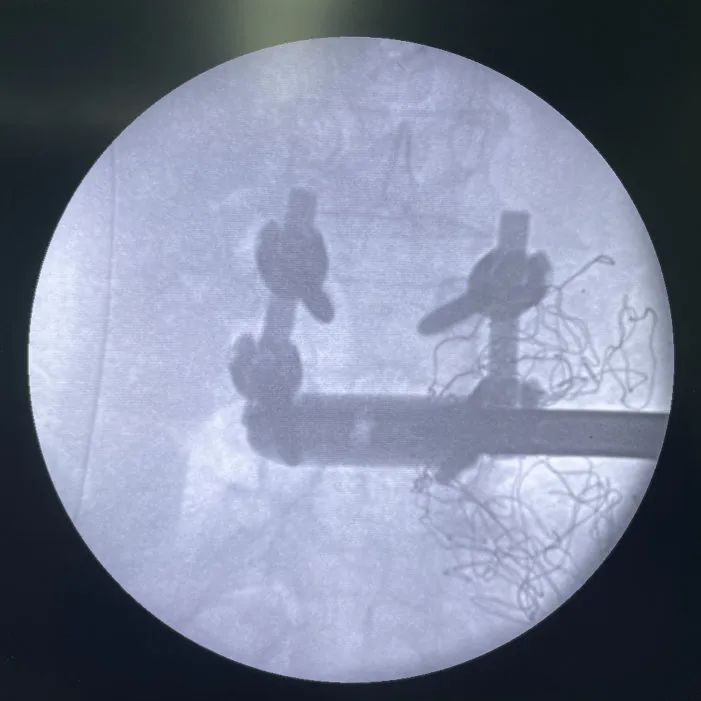

患者右側(cè)臥位,透視確認(rèn)皮膚切口區(qū)域

切皮暴露,透視確認(rèn)手術(shù)節(jié)段

最終透視